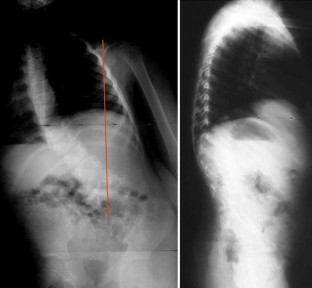

Fig. 5